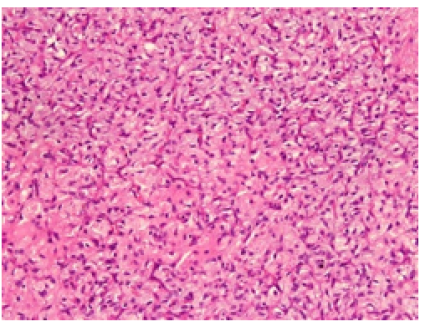

Embroiled and Tangled-Angiofibroma of Soft Tissue

Anubha Bajaj. 22(5): 134-138.